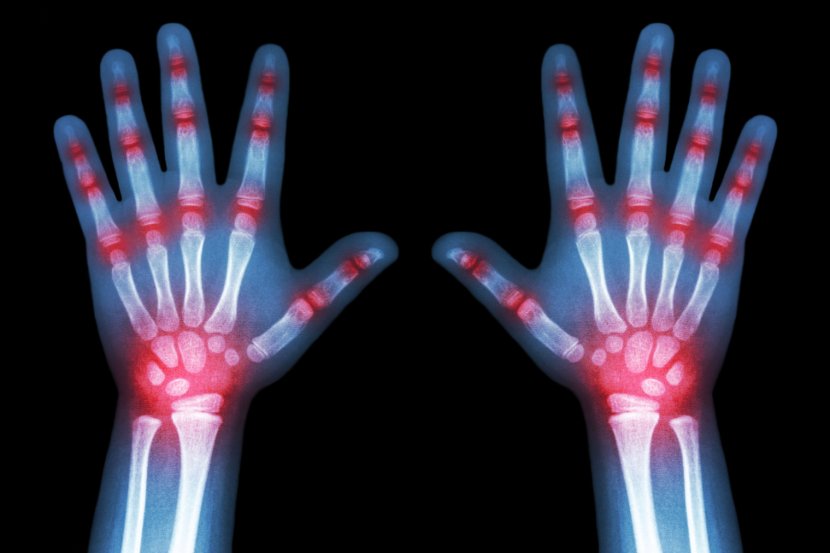

Tokom fizičkog pregleda, lekar proverava ima li otoka, crvenila i znakova upale, uz procenu opsega pokreta

Reumatoidni artritis je hronično reumatsko zapaljensko oboljenje. Najčešće zahvata zglobove, ali može da utiče i na unutrašnje organe, kožu i nervni sistem.

Tokom fizičkog pregleda, lekari testiraju zglobove na prisustvo otoka, crvenila i toplote. Takođe, želeće da vide koliko dobro možete da pokrećete zglobove.

• Rendgen (X-zraci): Koristeći niske nivoe zračenja za prikaz kostiju, rendgenski snimci mogu pokazati gubitak hrskavice, oštećenje kosti i izrasline na kostima (osteofite). Rendgen možda neće otkriti rane promene izazvane artritisom, ali se često koristi za praćenje napredovanja bolesti.